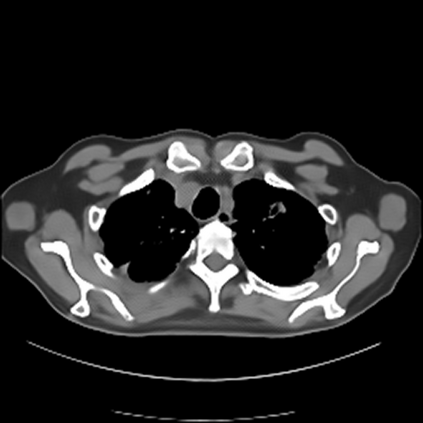

Sparse-view computed tomography (CT) -- using a small number of projections for tomographic reconstruction -- enables much lower radiation dose to patients and accelerated data acquisition. The reconstructed images, however, suffer from strong artifacts, greatly limiting their diagnostic value. Current trends for sparse-view CT turn to the raw data for better information recovery. The resultant dual-domain methods, nonetheless, suffer from secondary artifacts, especially in ultra-sparse view scenarios, and their generalization to other scanners/protocols is greatly limited. A crucial question arises: have the image post-processing methods reached the limit? Our answer is not yet. In this paper, we stick to image post-processing methods due to great flexibility and propose global representation (GloRe) distillation framework for sparse-view CT, termed GloReDi. First, we propose to learn GloRe with Fourier convolution, so each element in GloRe has an image-wide receptive field. Second, unlike methods that only use the full-view images for supervision, we propose to distill GloRe from intermediate-view reconstructed images that are readily available but not explored in previous literature. The success of GloRe distillation is attributed to two key components: representation directional distillation to align the GloRe directions, and band-pass-specific contrastive distillation to gain clinically important details. Extensive experiments demonstrate the superiority of the proposed GloReDi over the state-of-the-art methods, including dual-domain ones. The source code is available at https://github.com/longzilicart/GloReDi.